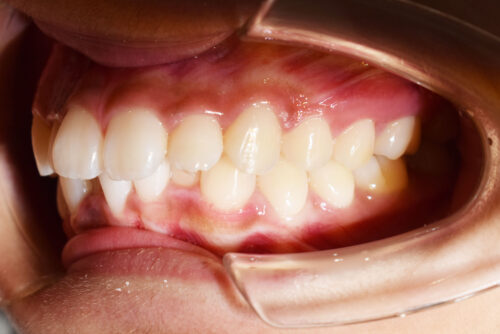

ワイヤー矯正治療7か月後です。

本症例も

矯正治療の精密検査後

非抜歯矯正治療計画を立案しました。

本症例のように

歯科矯正用アンカースクリュー(デュアル・トップオートスクリュー)を利用し

下顎のオートローテーションを行うことで

歯を抜かない非抜歯矯正治療でも

E-lineを整えることができます。